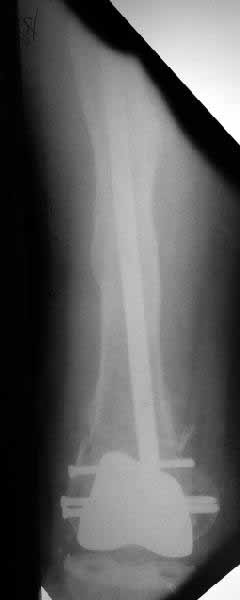

Well, finally i still performed antegrade nailing. After the distractor was applied, reduction of the recent fracture was obtained "automagically".

But the previous fracture resulted with some posterior displacment of the distal part, so antegrade nail would pass anteriorly, and retrograde nail, even a short one, would have penetrated anterior cortex proximally to the fracture. So perQ osteotomy was necessary to add some mobility at the level, and after that the nail was easily inserted to the distal fragment. The nail is solid, 13 mm, locking screws 6 mm. Locked statically.

The radiographs look excellent and a good outcome would be anticipated. The idea to osteotomize the femur shaft to compensate for the prior shaft malunion was clever and should work fine. I can't actually see the osteotomy on either radiograph. Is it more proximal than we see in these radiographsor so well aligned as to be not visible? Have you tried retrograde femoral nailing? Most people find it technically easier although not necessarily better than antegrade.